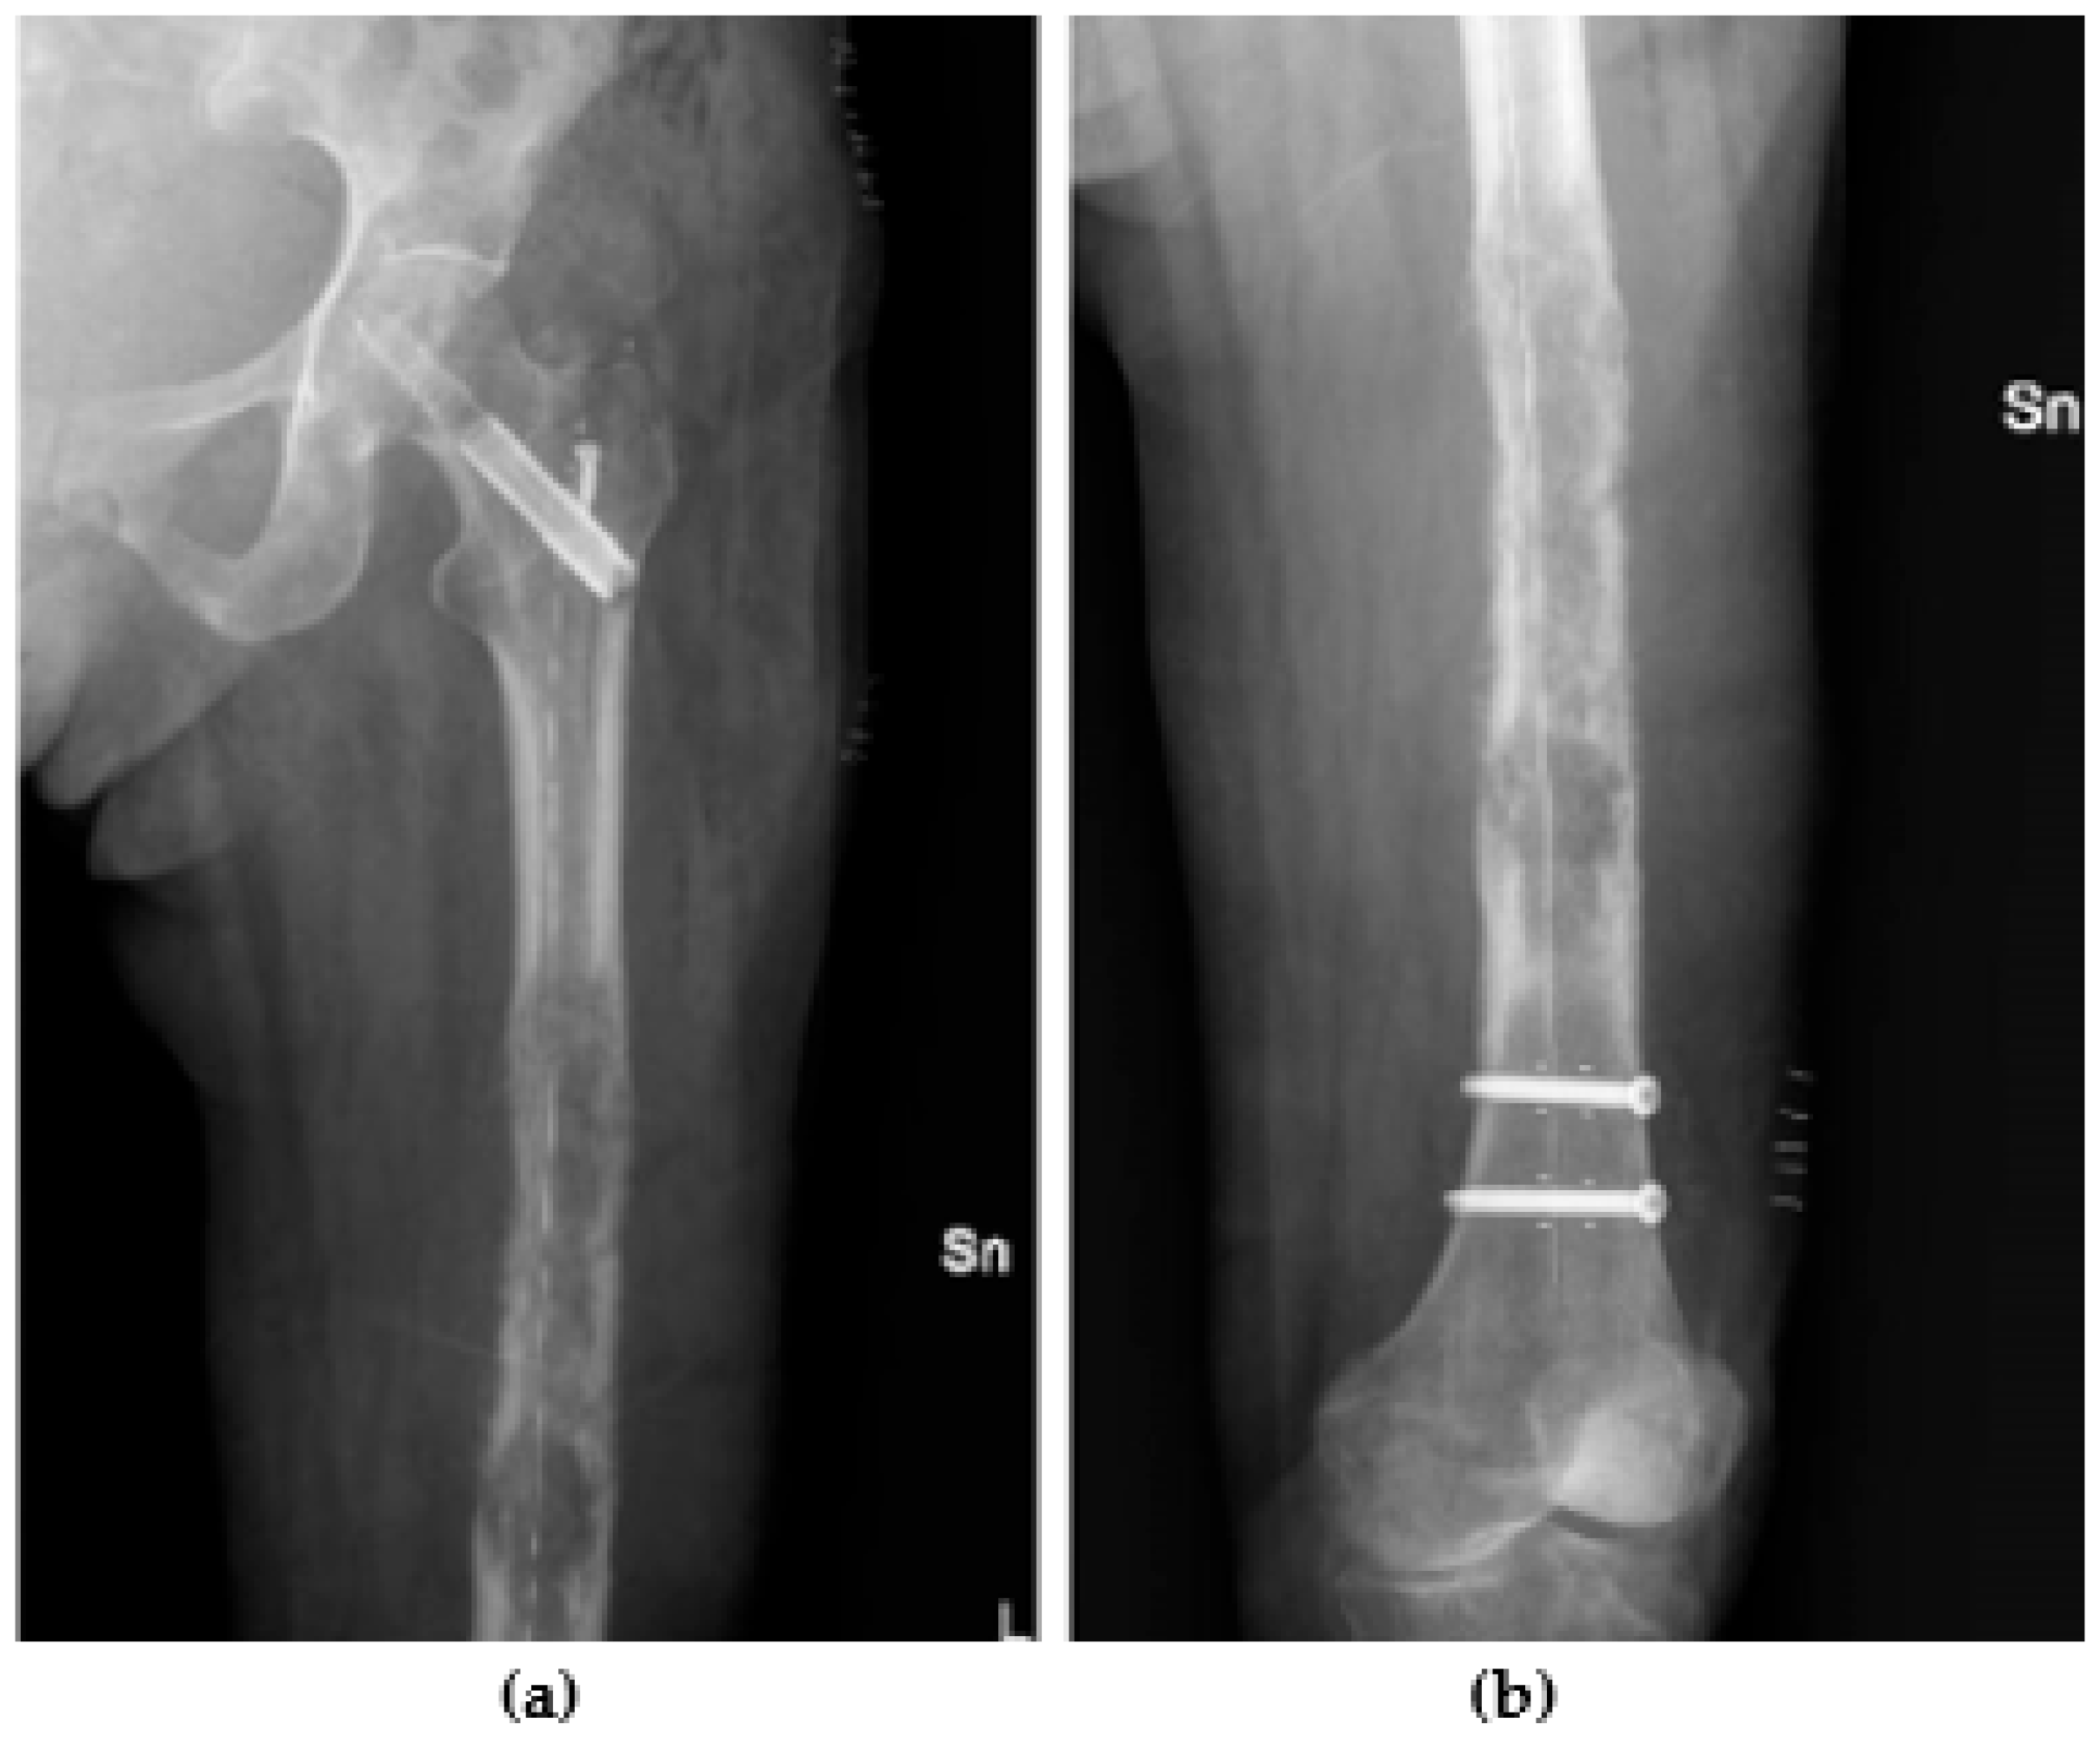

3.6. Radiolucency

- Takashima, K.; Nakahara, I.; Hamada, H.; Ando, W.; Takao, M.; Uemura, K.; Sugano, N. A carbon fiber-reinforced polyetheretherketone intramedullary nail improves fracture site visibility on postoperative radiographic images. Injury 2021, 52, 2225–2232. [Google Scholar] [CrossRef] [PubMed]